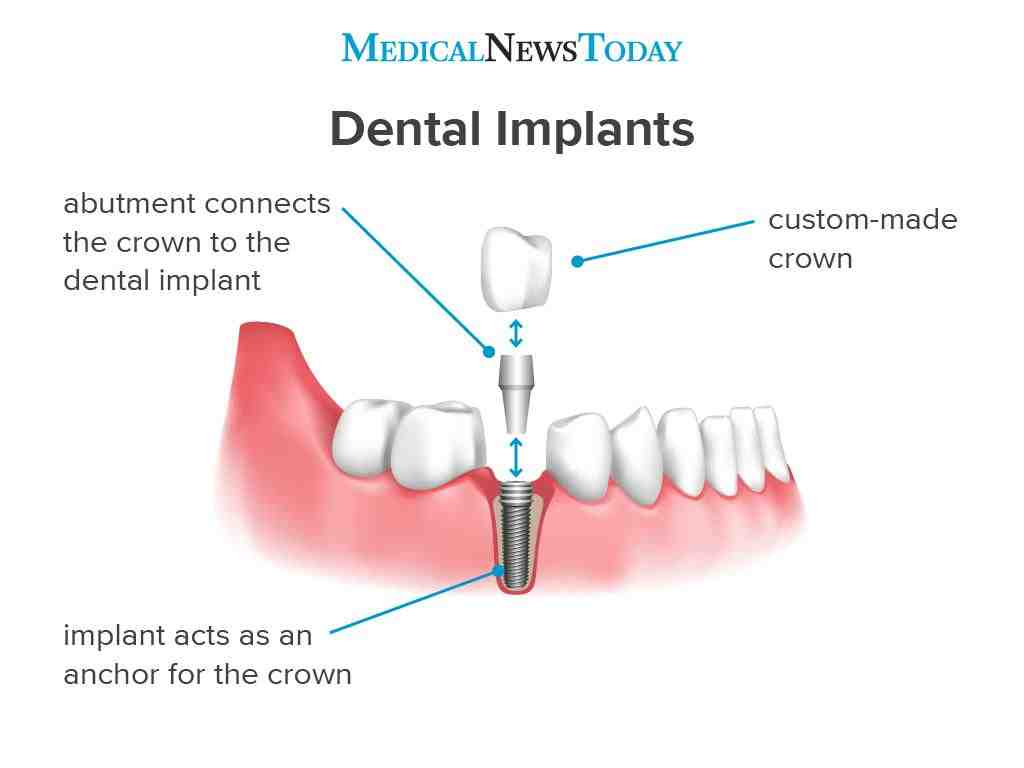

Dental implants can break if excessive pressure is applied before they have fully osseointegrated or bonded to the jawbone. Other parts of your new tooth can also break. Wear can cause the abutment, the tiny piece that connects the implant to the crown, to break.